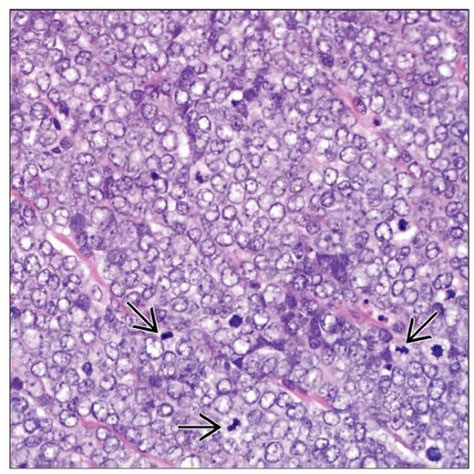

Merkel cell carcinoma (mcc) is a rare, aggressive form of skin cancer with a high risk for returning (recurring) and spreading (metastasizing) normal merkel cells in the skin: Merkel cells are connected to the nerve endings in the skin that are responsible for the sense of touch. They are nerve endings and provide information on mechanical pressure, position, and deep static touch features, such as shapes and edges. Merkel cells (mcs), the neuroendocrine cells of the skin, were believed to be at the origin of mcc due to their phenotypic similarities. Merkel nerve endings are mechanoreceptors, a type of sensory receptor, that are found in the basal epidermis and hair follicles. The tumour is centered in the dermis with frequent involvement of the overlying actinic keratosis and in situ squamous cell carcinoma is commonly found in the overlying skin (figure 2). The skin without hair is known as the glabrous skin; That's because gu and his research colleagues have proved that merkel cells— which contact many sensory nerve endings in the skin—are the initial sites for sensing touch.

After receiving a cancer diagnosis, your doctor will run tests to find out if the cancer has spread to other parts of your body. Merkel nerve endings are mechanoreceptors, a type of sensory receptor, that are found in the basal epidermis and hair follicles. Merkel cell carcinoma is a neuroendocrine carcinoma composed of densely blue cells. Merkel cells are found mainly at the base of the top layer of the skin (the epidermis). Merkel cells, found in the top layer of the skin, are very close to the nerve endings that receive the sensation of touch. Langerhans cells are dendritic but unpigmented and are found nearer the skin surface than melanocytes. They aid in the ability to sense light touch. They are associated with the sense of light touch discrimination of shapes and textures.

The tumour is centered in the dermis with frequent involvement of the overlying actinic keratosis and in situ squamous cell carcinoma is commonly found in the overlying skin (figure 2).

The skin over them is usually firm (not broken) and they don't hurt. Merkel cell carcinoma is highly treatable with surgical and nonsurgical therapies, particularly if caught early. In humans, merkel cells (yellow dot) are found clustered beneath the epidermal ridges (aka fingerprints). Merkel cells, found in the top layer of the skin, are very close to the nerve endings that receive the sensation of touch. However, for several reasons, for example, heterogeneous differentiation of mccs and postmitotic character of mcs, it is not very likely that mcc develops from differentiated. That's because gu and his research colleagues have proved that merkel cells— which contact many sensory nerve endings in the skin—are the initial sites for sensing touch. …contains two other cell types: The tumour is centered in the dermis with frequent involvement of the overlying actinic keratosis and in situ squamous cell carcinoma is commonly found in the overlying skin (figure 2).